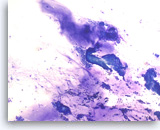

Ductal adenocarcinoma #2,

Pancreas FNA, Direct Smear.

The aspirates show single and clusters of malignant epithelial cells with unpredictable nuclear to cytoplasmic ratios. Metachromatic extracellular mucinous material is readily seen in the background as well as intermixed with epithelial cell clusters.

10X